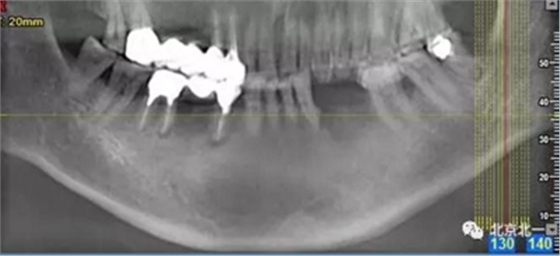

患者術(shù)前片, 最窄骨寬度僅僅3mm,34-35牙位缺失,

CBCT顯示如下圖